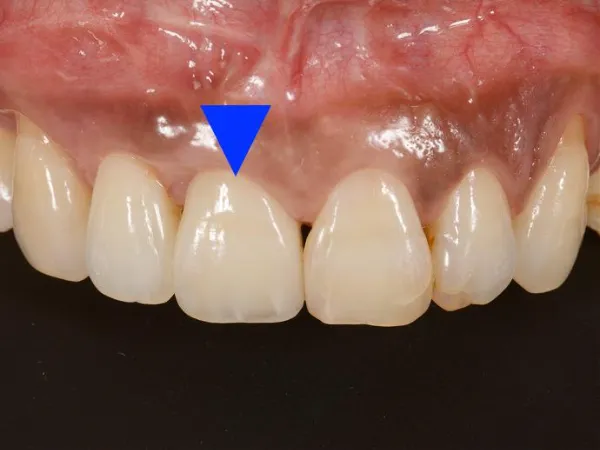

天然歯同様の審美性

インプラントは天然歯とほぼ変わらず、優れた審美性を実現します。